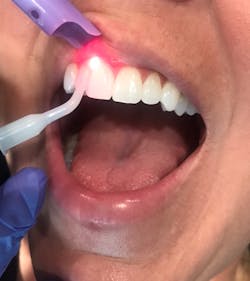

Depending on your state, some common procedures dental hygienists can perform with lasers are laser bacterial reduction (figure 1) and laser-assisted periodontal therapy (figure 2).1-3

Laser bacterial reduction (LBR) can be used to eliminate bacteria at any hygiene appointment prior to completing hygiene procedures. LBR is the practice of administering low-power laser energy within the sulcus throughout the entire dentition. This helps to reduce bacteremia, cross-contamination, and bacterial load, which, in turn, helps prevent attachment loss. This procedure is not used in the depths of periodontal pockets; it is more like a “preprocedural rinse.”4